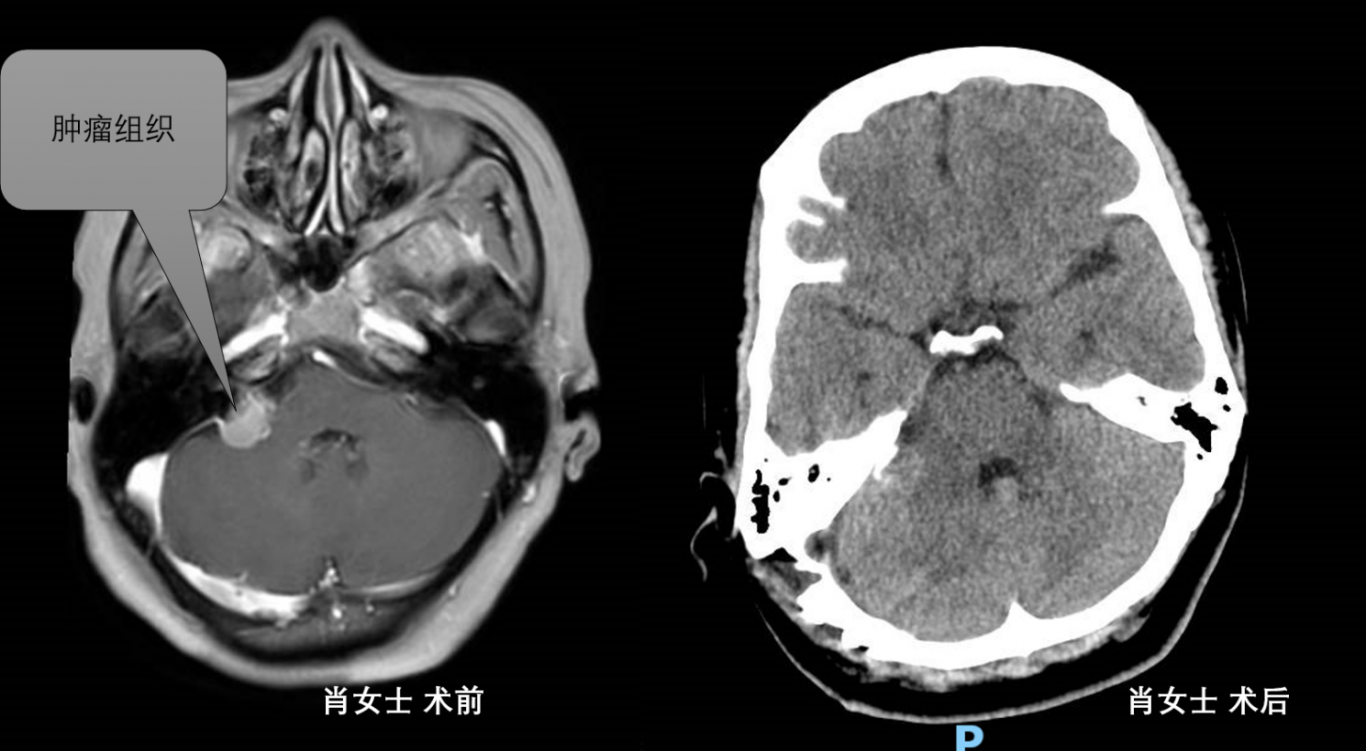

案例二:

江阳区肖女士,因反复头疼长达5年入院,头颅MRI提示右侧桥小脑角占位性病变。术后病检提示神经鞘瘤,术后2周,患者好转出院。